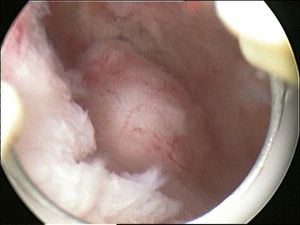

5. 1. 점막하 근종 (Submucosal myoma)

점막하 근종은 자궁 내막 아래의 근육에 위치하며 자궁강을 변형시킨다. 이 위치에 있는 작은 병변조차도 출혈 및 불임을 유발할 수 있다.[6] 강 내에 유경 병변은 자궁강내 근종이라고 하며 자궁 경부를 통과할 수 있다.2011년 이후 FIGO는 근종 분류에 대한 합의 논문을 발표했는데, 0부터 8까지 분류한다. 이는 PALM COEIN 분류의 일부이며 임상 실습 및 연구에서 가장 자주 사용된다.[19]

- ''자궁경 수술'' 근종 절제술(''경자궁경부 절제술''): 절제경, 질과 자궁경부를 통해 삽입하여 조직을 절단하는 데 고주파 전기에너지를 사용할 수 있는 내시경 도구를 사용하거나 이와 유사한 장치를 사용하여 자궁근종을 제거.